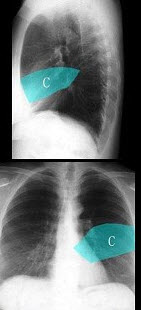

257、单项选择题

如图,在正常胸部X线影像图像上,该英文字母所代表的肺段为()

A.尖段

B.后段

C.尖后段

D.舌叶上段

E.前段